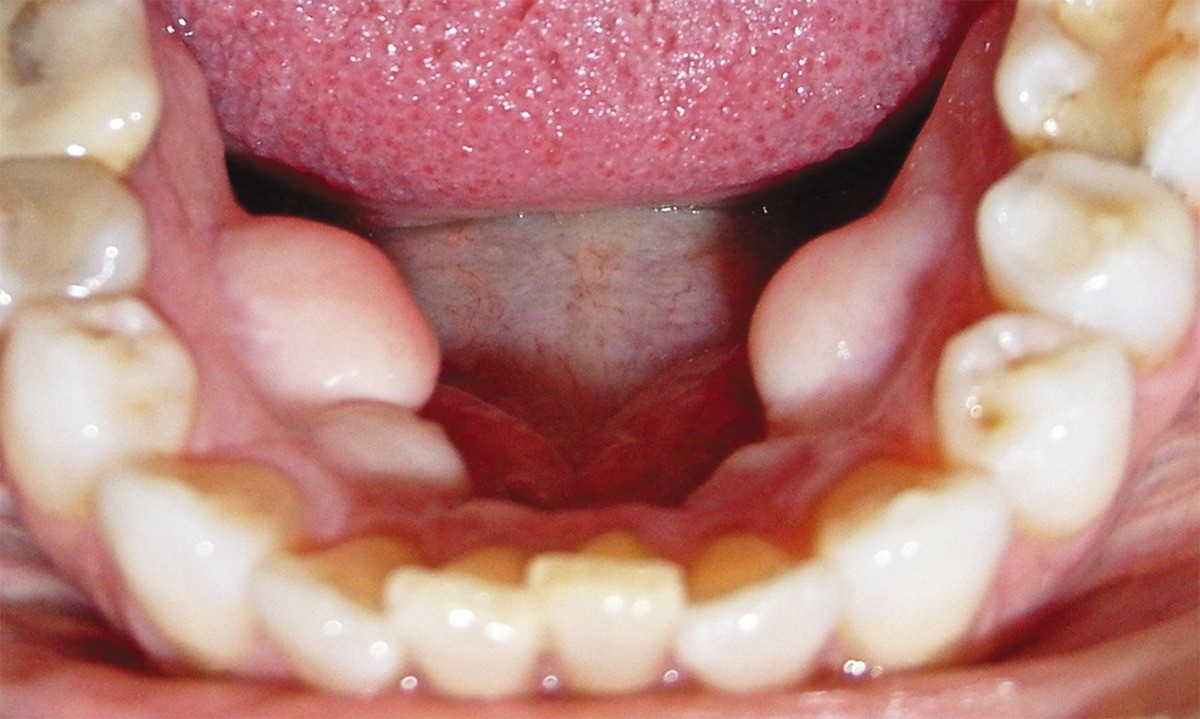

This condition presents as a bony growth beneath and on the side of the tongue. You may have one growth or multiple growths, and they can develop on one side of your mouth or on both sides. While it's usually asymptomatic, this condition can sometimes cause problems. If you wear dentures, the growth can interfere with the fit of your lower denture. Your denture may be uncomfortable and may not stay in place. The soft tissues that cover the growth can also become ulcerated in some cases.